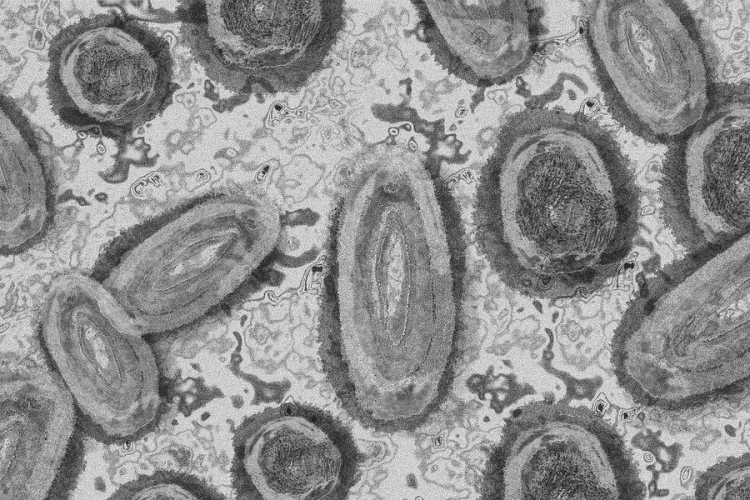

Meghaladta a 13 ezret a majomhimlő-fertőzöttek száma az Egyesült Államokban

Meghaladta a 13 ezret a majomhimlő-fertőzöttek száma az Egyesült Államokban, a legtöbb esetet Kaliforniában és New York államban regisztrálták.

Tovább nőtt a majomhimlő-fertőzöttek száma Magyarországon

Újabb kilenc, 23-50 éves férfinél igazolták a majomhimlő-fertőzést Magyarországon, ezzel 42-re nőtt a fertőzöttek száma - közölte a Nemzeti Népegészségügyi Központ (NNK) csütörtökön az MTI-vel.

Tovább nőtt a majomhimlő magyar fertőzöttjeinek száma

Újabb hat embernél diagnosztizálták a majomhimlő vírusát, így harmincra emelkedett az igazolt fertőzöttek száma Magyarországon - közölte a Nemzeti Népegészségügyi Központ (NNK) pénteken az MTI-vel.

Újabb hét magyarnál igazolták a majomhimlőt

Újabb hét embernél igazolták a majomhimlőfertőzést a Nemzeti Népegészségügyi Központ (NNK) veszélyes kórokozókkal foglalkozó laboratóriumában; ezzel 19-re nőtt az igazolt majomhimlő fertőzöttek száma Magyarországon